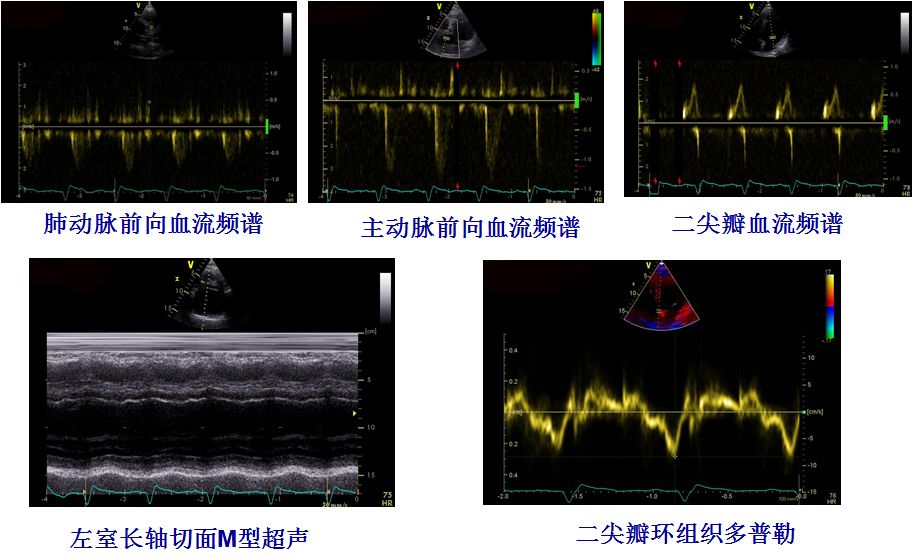

超声心动图评价CRT效果

超声心动指标对这类患者的心脏再同步化治疗术前筛选更有意义。

评价机械性不同步

超声心动指标对心脏再同步化治疗

术前术后的评价意义

术前超声评估、术后CRT效果评估为患者提供精准个体化的治疗